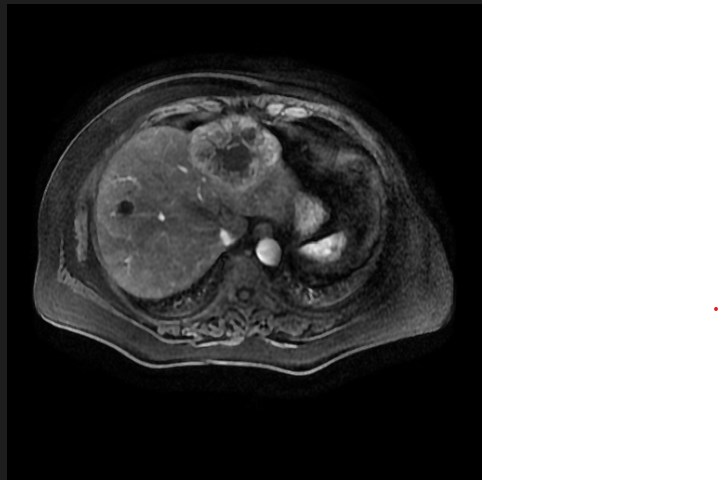

最后的得到的png图像与原图看起来没什么区别。